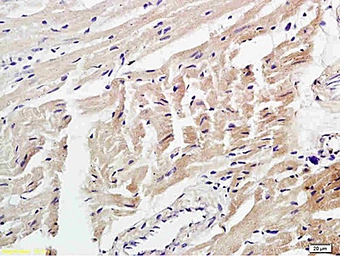

4 Hydroxynonenal antibody

Cat. No. GTX01087

ApplicationsWB IHC-P IHC-Fr ELISA

ReactivitySpecies independent